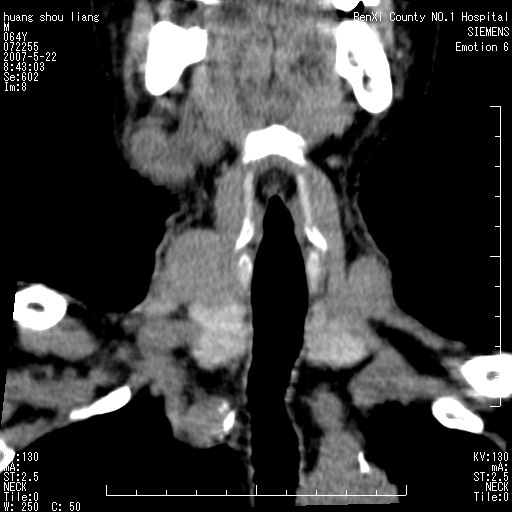

男性,64岁。颈部包块8年。最近增大。

对不起大家,可能是片子发太多有点乱,正常腮腺在下颌角的外侧,颌下腺在下颌体的中部内侧,本例在下颌角内侧偏下,和腺体一点关系都没有,从vrt和mpr上可以很明显看出来,再者肿块是好多粘连在一块的,大家在仔细看看,左侧可能也是吧,我还是考虑为肿大的淋巴结融合在一块,但性质??????

右侧腮腺下部均匀软组织密度肿块,外形不规则,与周围组织分界清晰,考虑右侧腮腺混合瘤或多形性腺瘤。

大家好,病理结果出来了,如大家所说,颌下腺混合瘤。

唉,解剖没学好吧,我诊断错了,不过还是有些不理解回去我在多看看书,谢谢大家的参与,以后我还会奉献好的病例。